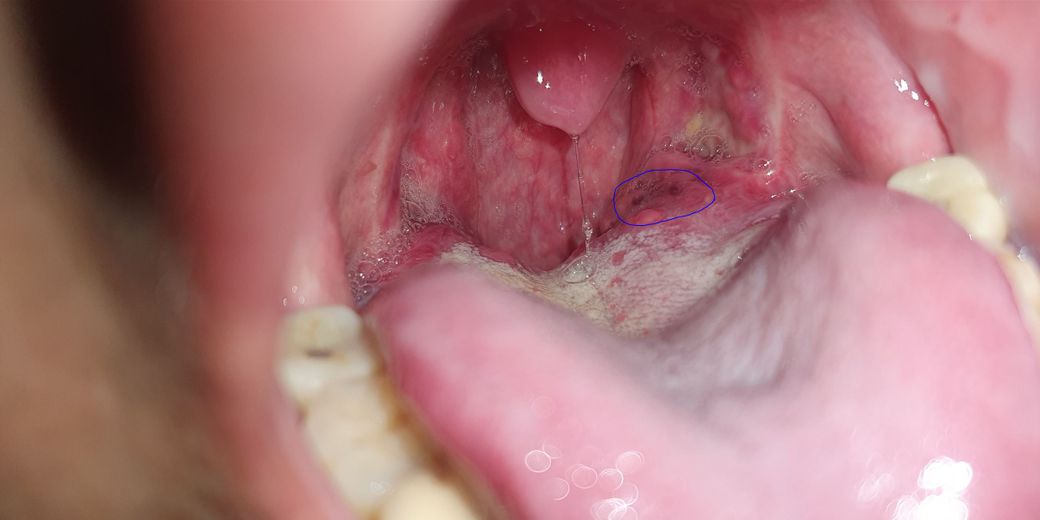

일주일 전부터 혀 뿌리 쪽에 욱신거림과 때때로 바늘로 찌르는 듯한 통증이 느껴집니다.

위 사진에 표기한 부분에서 통증이 느껴지며 검은 구멍이 2개 있는데 무슨 병 일까요?

• 1번 째 사진

해당부위에 검은 구멍은 구강내 정상적인 구조로 특별히 병이 있거나 하지는 않습니다. 하지만 통증이 지속되는 경우에는 보다 정밀하게 현재 상태 확인을 위해 구강검진을 받아보길 권합니다.